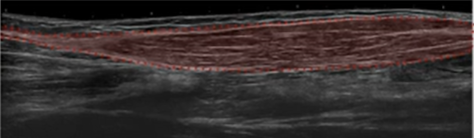

Anatomie interne des muscles

MOREL M. - Hôpital R. Salengro - CHRU LILLE

MAP 2006

Musculo-squelettique Muscle MAP